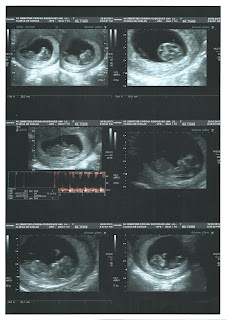

E pronto, a primeira eco está feita, se bem que tem de ser repetida daqui a 2 semanas. O feto ainda é pequenino para tirar as medidas todas mas apresenta-se perfeitamente dentro do percentil expectável para um feto com 11 semanas certas. :)

Resumindo a parte "burocrática" o feto apresenta-se com um crânio/cérebro "aparentemente normal", o coração "aparentemente normal", as mãos "ambas visíveis" e pés "ambos visíveis". Frequência cardíaca de 161 bpm e CCC de 42,7mm.

"Gravidez de 11 semanas. Boa dinâmica fetal. Sem malformações aparentes nesta idade de gestação. Sugere-se novo exame dentro de 1-2 semanas para DPN."